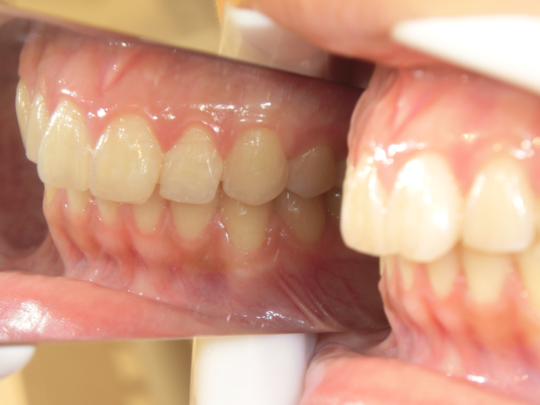

治療後

治療の副作用(リスク)歯の動き方には個人差があり、予想された治療期間が延長する可能性があります。。マウスピースの使用状況、矯正歯科治療には患者さんの協力が必要であり、それらが治療結果や治療期間に影響します